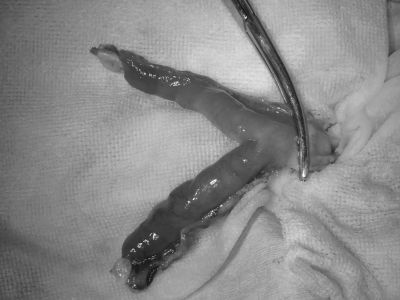

放置すると敗血症やショックに進行してしまう可能性があるため、すぐに手術で感染した子宮卵巣の摘出を行いました。